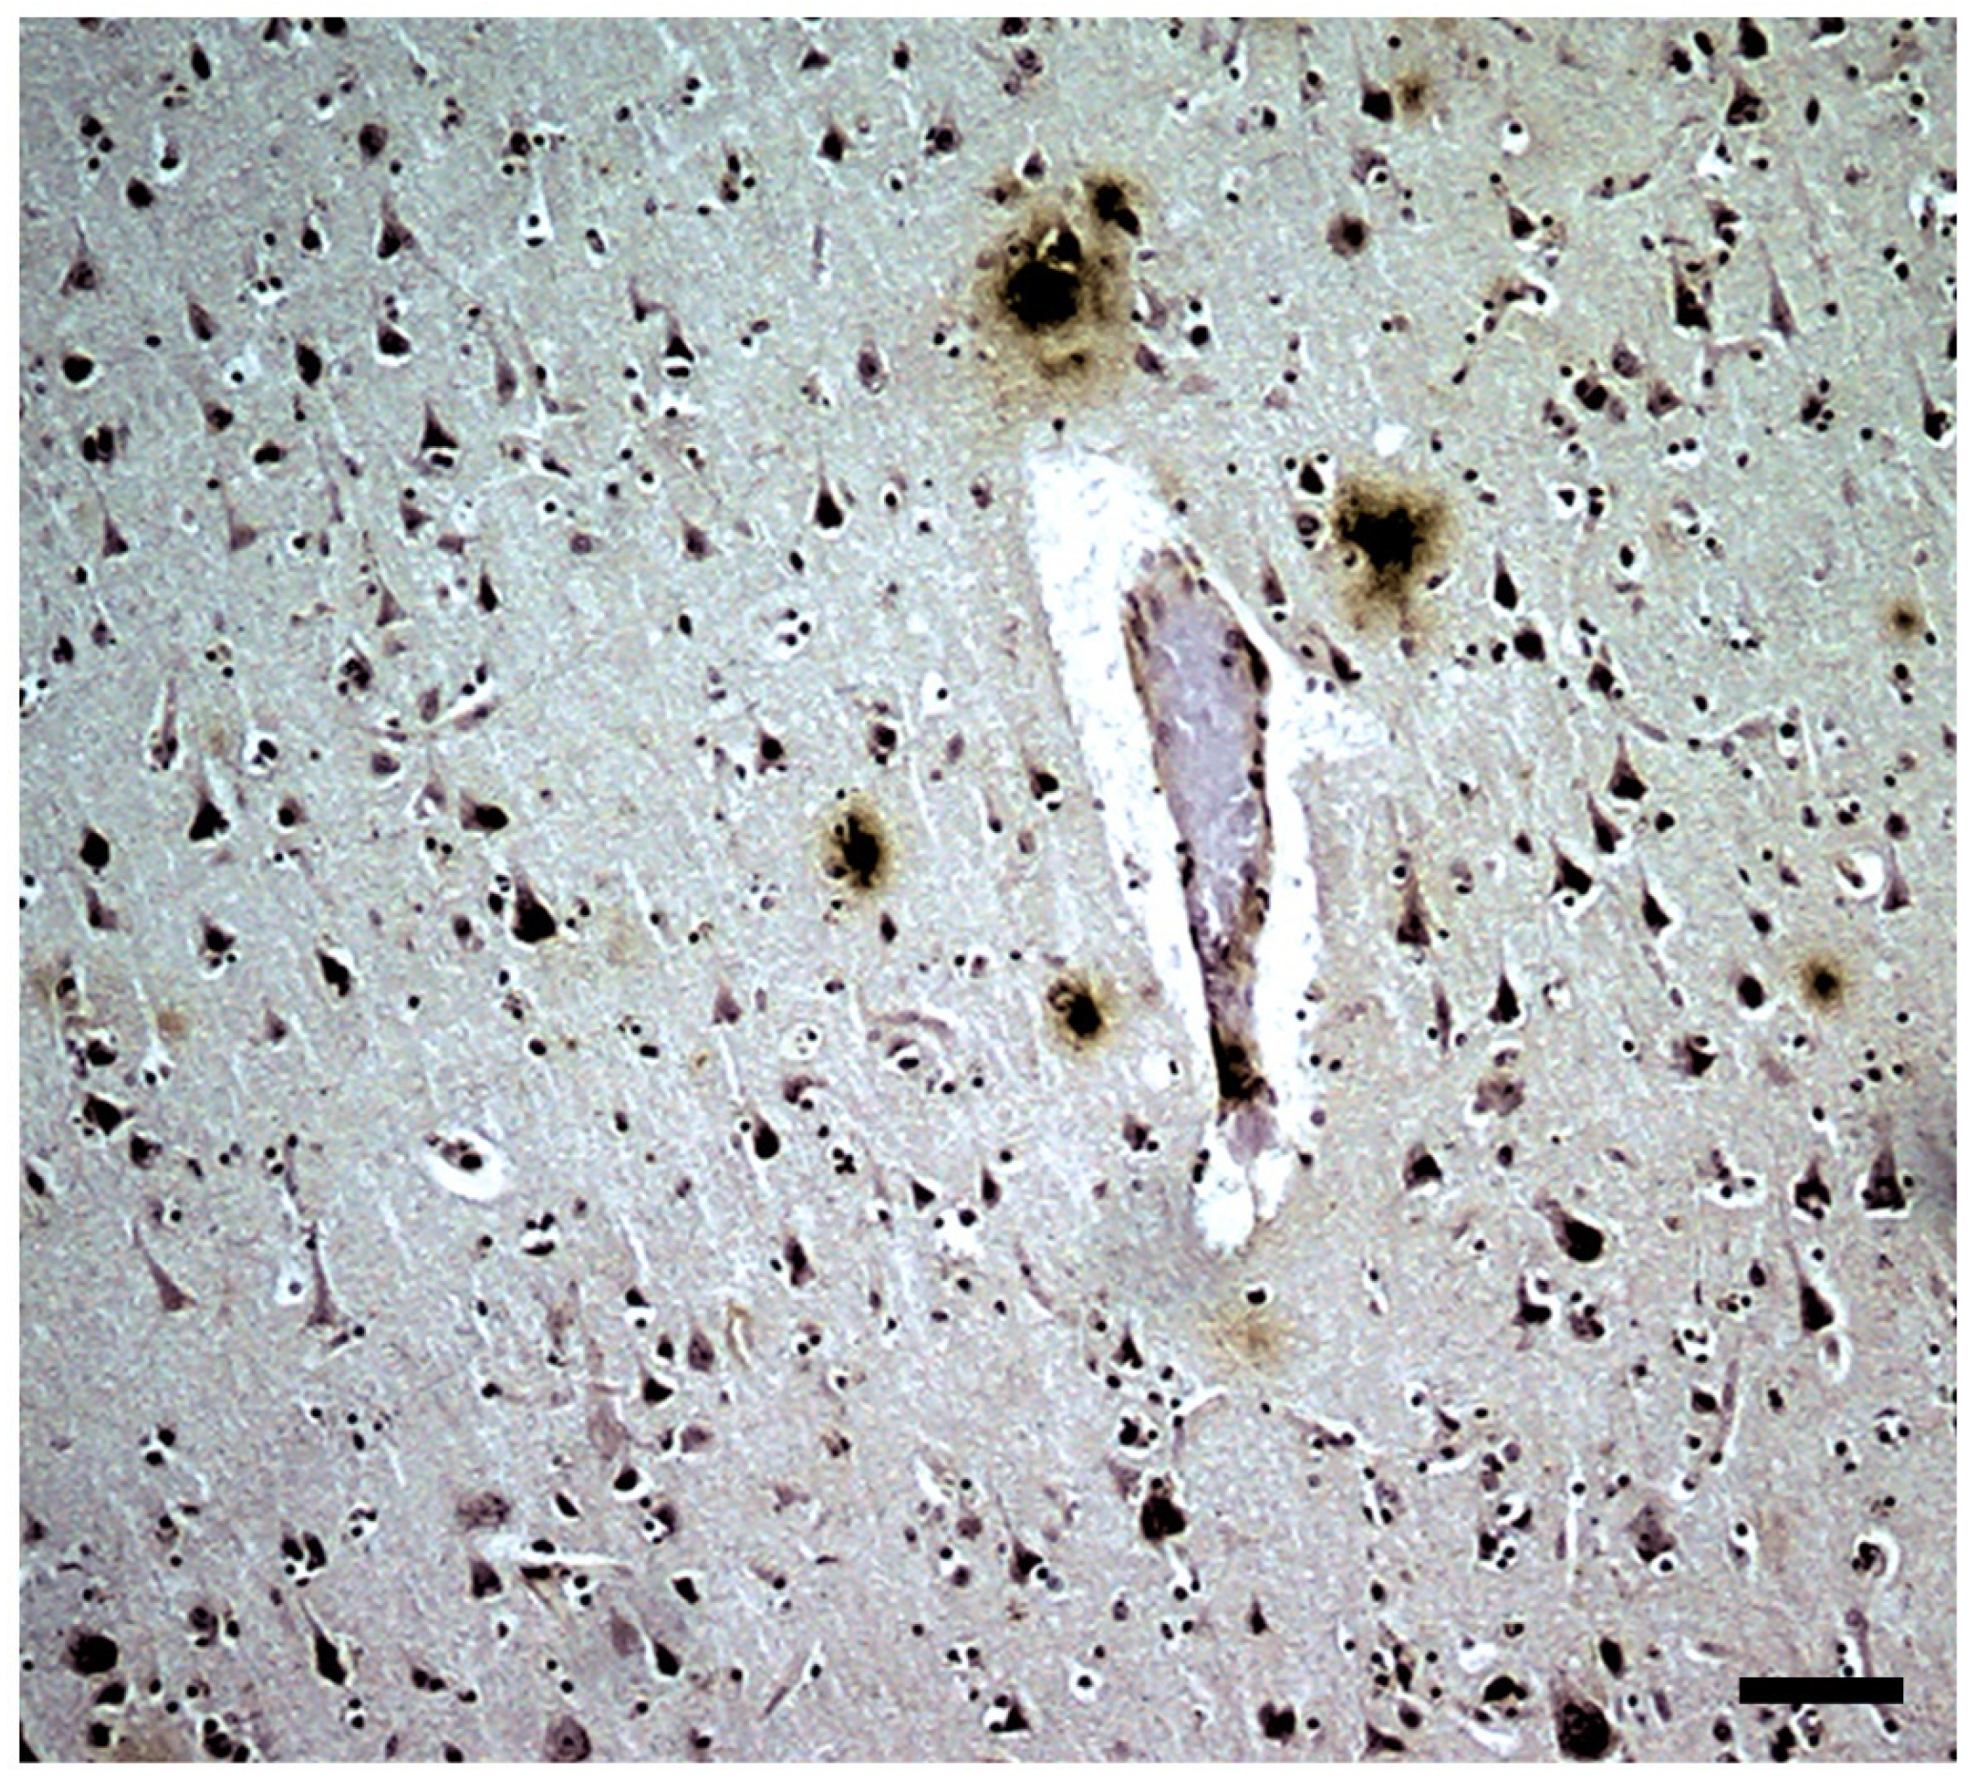

| NEUROPATHOLOGICAL AND NEUROGLIAL CHANGES IN A T2D-AD MOUSE MODEL (APP+PS1 MICE ON A HIGH-CALORIE DIET) Material and Methods (abstract) Animals Control mice (wild type—WT): C57BL/6 (males). Transgenic mice: APPswe/PS1dE9 (APP/PS1) transgenic mice. Diets tested: (a) standard control diet in the animal facility (cd); (b) high-calorie diet: 47% carbohydrates, 21% fat, 1.3% cholesterol (high-fat/hipercaloric diet) (hcd). Trial groups (4) and number of animals in each group: 1- Control WT animals with a standard diet (12). 2- Control WT animals with a hypercaloric diet (12). 3- Transgenic APP/PS1 animals with a standard diet (12). 4- Transgenic APP/PS1 animals with a hypercaloric diet (12). Duration of the trial: 5 months (from 1 to 6 months of age). The diets were used from the first month of life. The samples were obtained at 2, 3, and 6 months of life of the animals. Obtaining and processing of brains and other tissue samples: At 2, 3, and 6 months of treatment, twelve animals were randomly selected from each group. Of these animals from each group, six were decapitated, and the brain (from which the frontoparietal cortex and hippocampus were isolated) and the liver were removed. Homogenates were obtained and stored at −20 °C. The rest of the animals were perfused with 4% p-formaldehyde after anesthesia. The fixed brains were sectioned coronally, obtaining serial sections for histological and immunohistochemical staining, as well as thioflavin-S staining. Some small pieces of these sections were impregnated with osmium tetroxide and processed in Araldite to be observed under an electron microscope. Liver samples were processed for optical and electron microscopy studies. Histopathological studies and quantitation: Various antibodies were used to characterize neurons, astroglial cells (GFAP, C-1 complement), microglial cells (IBA-1, CD 68, lectins), APP, and phospho-tau. Using the Nikon microscope image analysis systems, the number of astroglia and microglia cells, as well as amyloid deposits in selected areas (6 areas per slice × 10 slices) in both the frontoparietal cortex and the hippocampus (CA-1 and CA3), were quantified. Statistical study: The data were obtained from each individual in each group, as well as the mean +/− SEM for each group. For data presentation, the percentage increases in each group over the mean value of group 1 (control animals on a standard diet) were used, considered 100%. Differences between groups were considered significant at p < 0.05. |